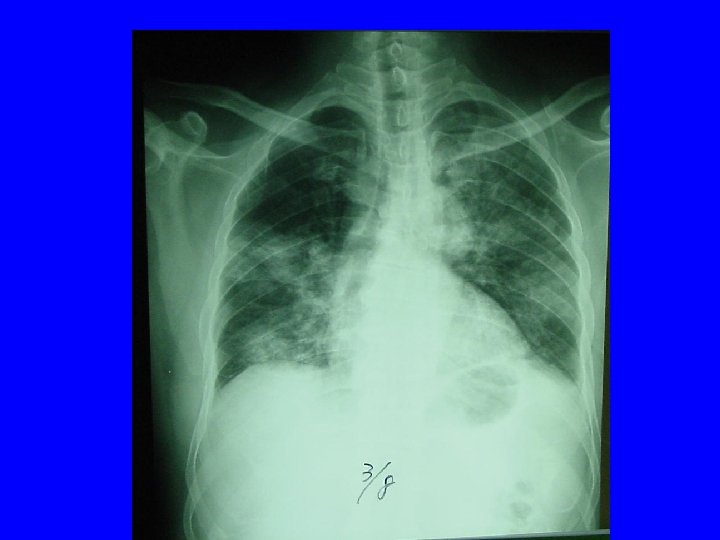

Radiology of typical case Lee NEJM 4/7/04

Radiographic Features of SARS • Infiltrates present on chest radiographs in > 80% of cases • Infiltrates – initially focal in 50 -75% – interstitial – Most progress to involve multiple lobes, bilateral involvement

Lee N. et al NEJM 4/7/03